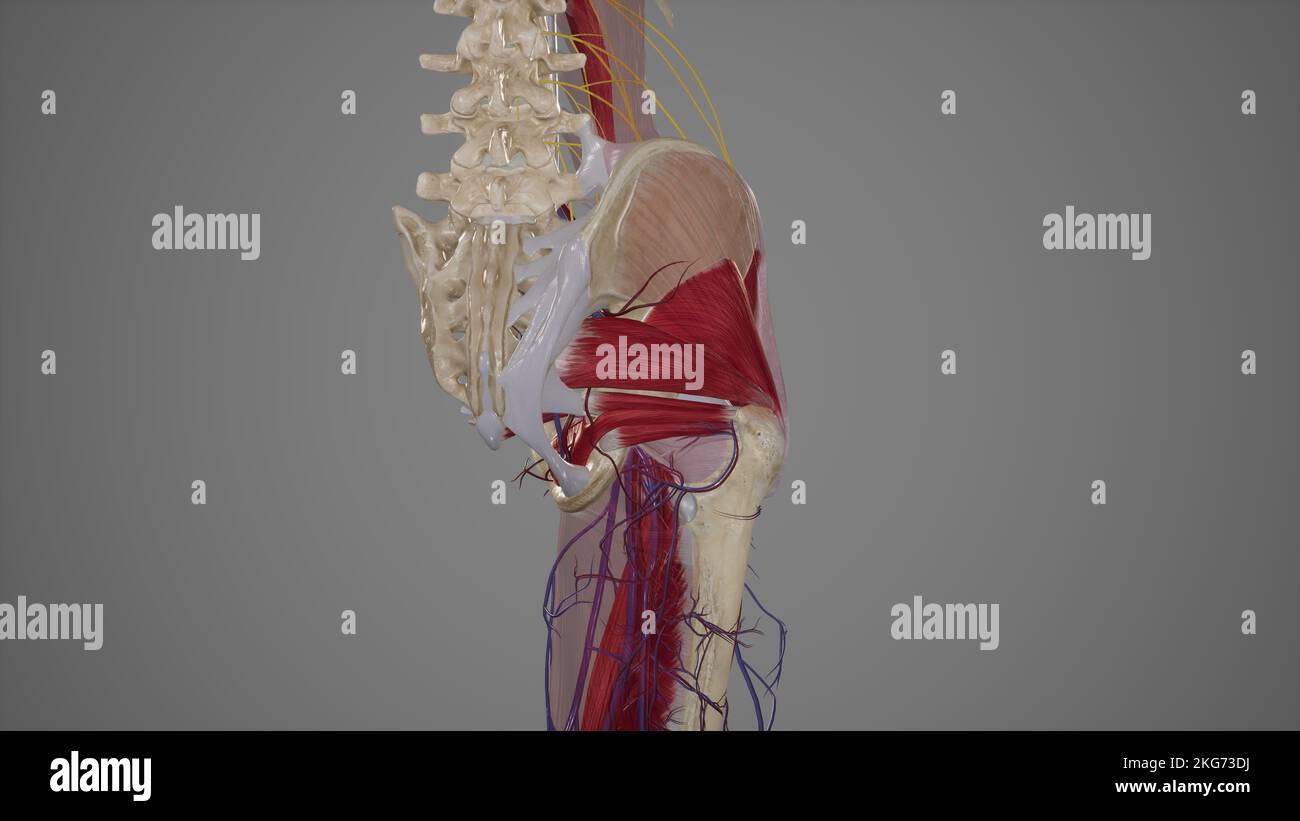

Arteries of Gluteal Region Stock Photohttps://www.alamy.com/image-license-details/?v=1https://www.alamy.com/arteries-of-gluteal-region-image491881198.html

Arteries of Gluteal Region Stock Photohttps://www.alamy.com/image-license-details/?v=1https://www.alamy.com/arteries-of-gluteal-region-image491881198.htmlRF2KG73DJ–Arteries of Gluteal Region